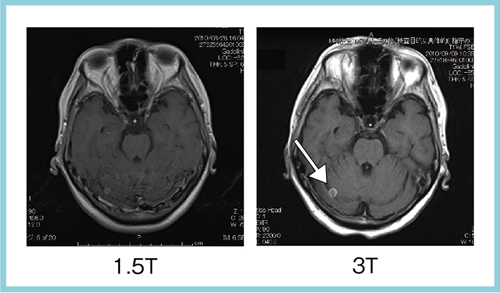

肝の最新MRI 伸弘, 谷本

金原出版

2004/5/1